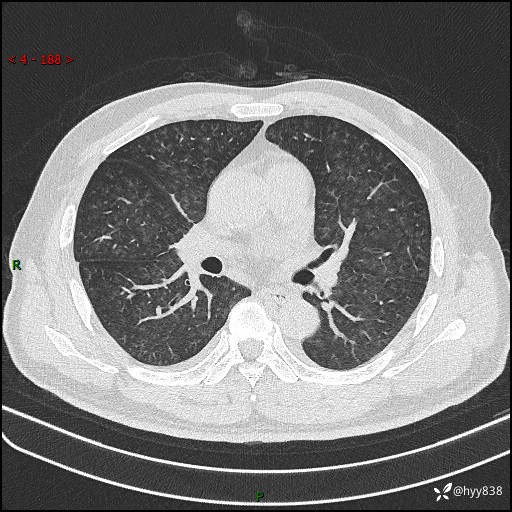

辅助检查:CT

胸部HRCT